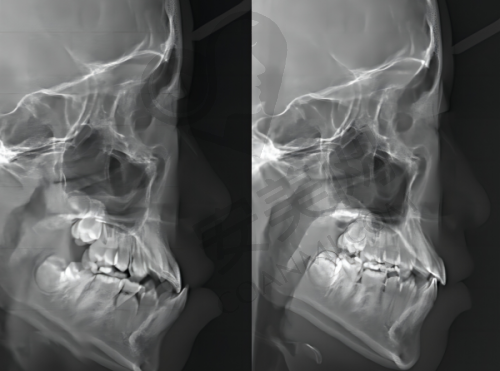

我第一次来到深圳铭德口腔,前台的工作人员非常热情地接待了我,引导我填写了相关的信息表格,包括个人基本信息、牙齿状况以及既往病史等。填完表格后,护士带我去拍了牙齿的X光片和口腔的全景照片,这些检查可以帮助医生全方面了解我的牙齿和颌骨的情况。之后,我见到了为我进行矫正的医生,医生非常耐心地查看了我的检查结果,和我沟通了我的牙齿问题,比如牙齿拥挤、咬合不正等,还详细地给我介绍了几种适合我的矫正方案,包括传统金属牙套、陶瓷牙套和隐形牙套,并分析了每种方案的优缺点和价格。在医生的专精建议下,我结合自己的需求和经济情况,选择了隐形牙套矫正方案。